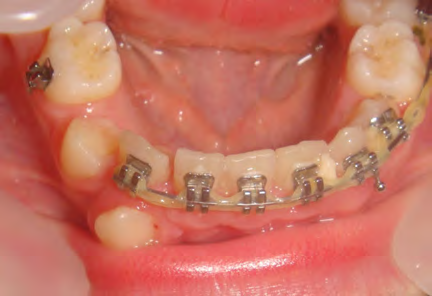

All of the patients below had been told they required extractions by orthodontists, some insisting that they could not be treated without extractions.

They were all treated without extractions, head gear or facemasks at Vakresmil and represent just a small sample of cases treated between 2004–2014.

The patient below had severe crowding of both upper canines and the lower right 5. The upper 4’s and 2’s were actually in contact.